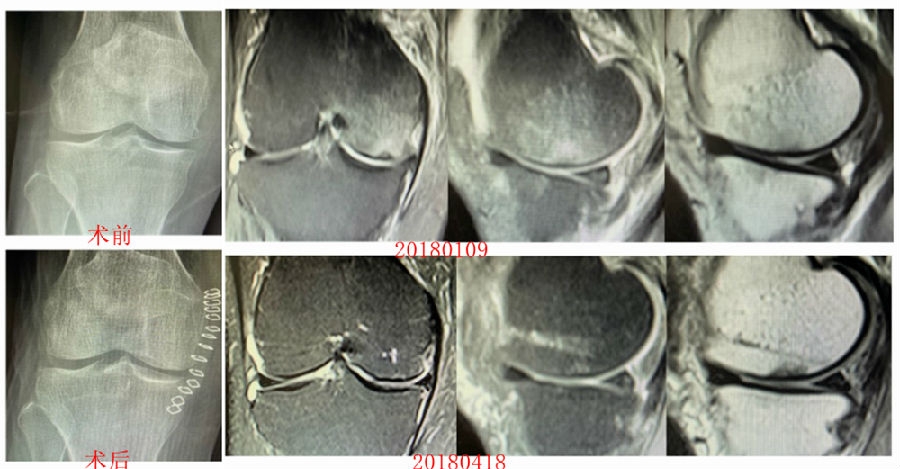

病例1:女,65岁,主诉右膝关节内侧疼痛1周。2018年1月X光未见右膝骨质异常,MR检查见股骨内侧髁骨坏死,半月板相对突出百分比(RPE)28.99%,关节线会聚角1.4°。

予切开行克氏针钻孔减压,口服消炎止痛药物、钙剂及骨化三醇,不负重6周,后改部分负重至3个月。2018年4月复查MR见骨髓水肿基本完全吸收,坏死区局限并修复良好,半月板相对突出百分比(RPE)32.08%,患者临床症状消失。